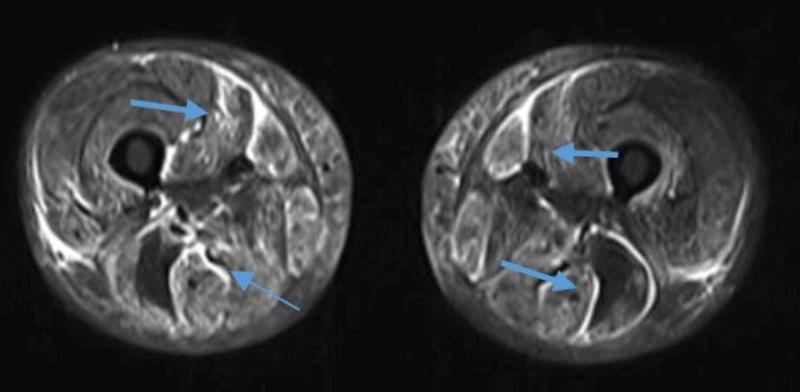

Antisynthetase syndrome is an autoimmune condition that manifests clinically through signs and symptoms, such as interstitial lung disease, myositis, Raynaud's phenomenon, fever, hyperkeratotic fingertips (mechanic's hands), and arthritis. It is associated with antibodies against aminoacyl tRNA synthetase enzyme, the most common autoantibody being the anti-Jo-1. An 18-year-old girl presented with weakness of both the upper and lower limb, swelling and generalized body pain, difficulty in swallowing. MRI of the thigh was highly suggestive of myositis with symmetrical bilateral involvement. Based on proximal muscle weakness, elevated creatine phosphokinase (CPK), and lactate dehydrogenase (LDH), strongly positive anti-nuclear antibodies human epithelial cell type-2 (ANA-HEp2), and a normal nerve conduction velocity test with precise MRI findings, a diagnosis of polymyositis was made. She was given bolus intravenous methylprednisolone for five days, followed by oral methylprednisolone with subcutaneous methotrexate weekly. She reported a 50% improvement in muscle weakness; however, partial bulbar weakness persisted at the time of discharge. On her next follow-up, her blood investigations for auto-antibodies were done. The autoantibodies anti-Jo-1 (3+), Ro-52 (2+), and Mi-2β (2+) were found to be positive. These investigations, coupled with the clinical features she was presenting, finally led us to conclude that it was a case of polymyositis complicated by the antisynthetase syndrome.